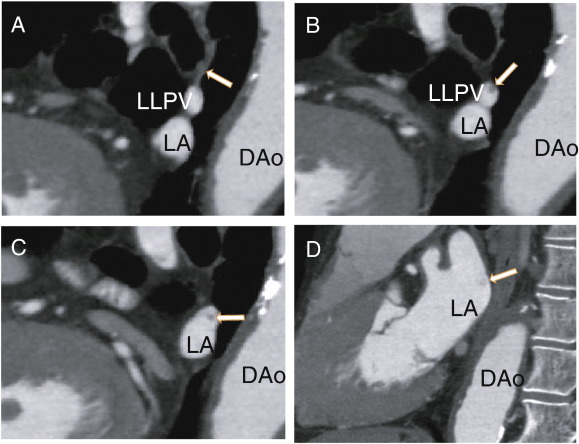

The patient was a 78-year-old male who presented with chest pain and had no previous treatment with warfarin. D-dimer was less than 0.5 μg/ml (normal value < 1.0 μg/ml), protein S activity was 91% (normal range 60–150%), and protein C activity was 66% (normal range 64–146%). He was treated with aspirin (82 mg i.d.) as an antiplatelet therapy. The patient was referred to our hospital for the evaluation of coronary artery stenosis. The chest roentgenogram was negative for lung cancer. The patient had no symptoms of cough, cerebral infarction or cancer, and the patient had no history of either catheter ablation or lung surgery. A 64-MDCT scan showed a pulmonary vein thrombus (Fig. 1); however, there were no thrombi in the left lower pulmonary vein (LLPV) at first. A non-contrast enhanced vessel, which might have been completely occluded, approached from the upper side (Fig. 2A). There, a non-contrasted branch of the pulmonary vein at the upper side of the LLPV was observed (Fig. 2B), which extended proximally in keeping the position on the upper side of LLPV (Fig. 2C). The contrast enhancement defects did not diffuse and enter the LA (Fig. 2D).

A: Sagittal images showing the left lower pulmonary vein and the non-contrast ...

Fig. 2.

A: Sagittal images showing the left lower pulmonary vein and the non-contrast small pulmonary vein (arrow). B: Sagittal images showing the thrombus in the left lower pulmonary vein as a defect of small enhancements (arrow). C: Sagittal images showing the larger pulmonary vein thrombus, which was separate from the wall of the left lower pulmonary vein (arrow). D: Sagittal images showing the thrombus in the left atrium (arrow). DAo: descending aorta, LA: left atrium, LLPV: left lower pulmonary vein.